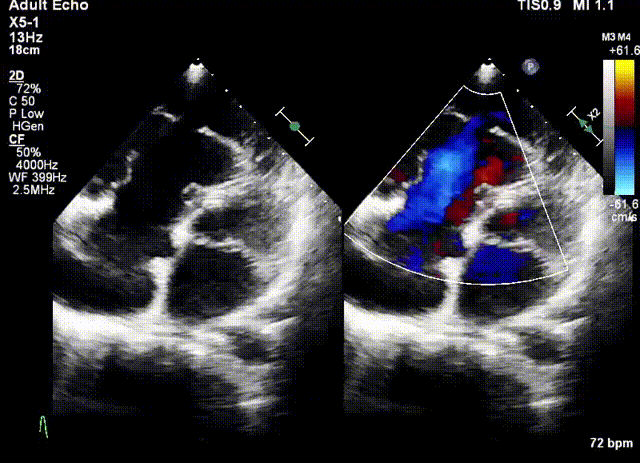

術前超聲

術中超聲